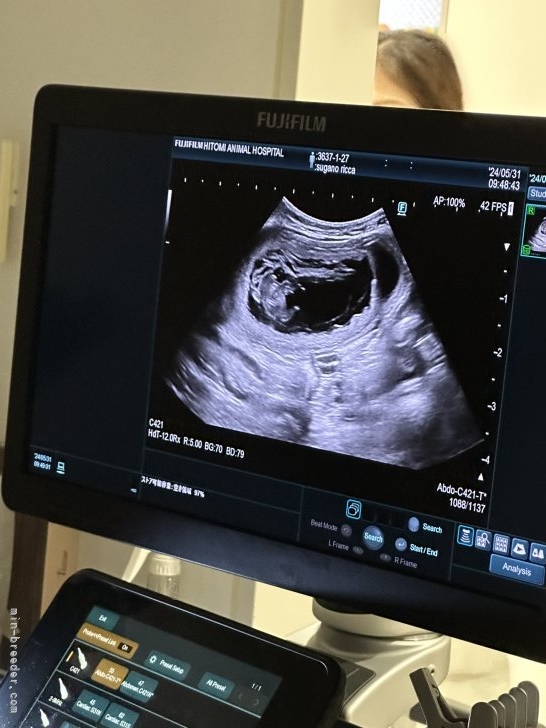

祝ご懐妊(トイプードル)今日、獣医さんでエコー検査。 何匹いたかは、生まれる直前のレントゲン の時に、発表させていた...